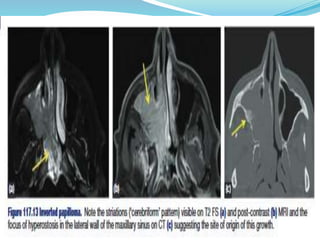

 CT Scan with contrast –hyper dense areas and

calcification (linear). Bony destruction & Erosion of

the lateral wall

 MRI .. Intracranial & extra cranial extension .

Enhancing mass with heterogeneous conveluted

cerebriform appearance -- characteristic